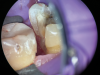

(8.) Close-up occlusal view of a maxillary first molar after the removal of deep subgingival caries, where despite rubber dam isolation, infiltration of blood and saliva into the cavity has occurred.

(9.) Close-up occlusal view of the maxillary first molar prepared for a matrix-in-matrix technique with a circumferential matrix supported by a 3-mil copper band inside for proper adaptation to the margin’s concave and convex areas. Note the addition of a liquid dam material placed between the two matrices for added stability.

Figure 9